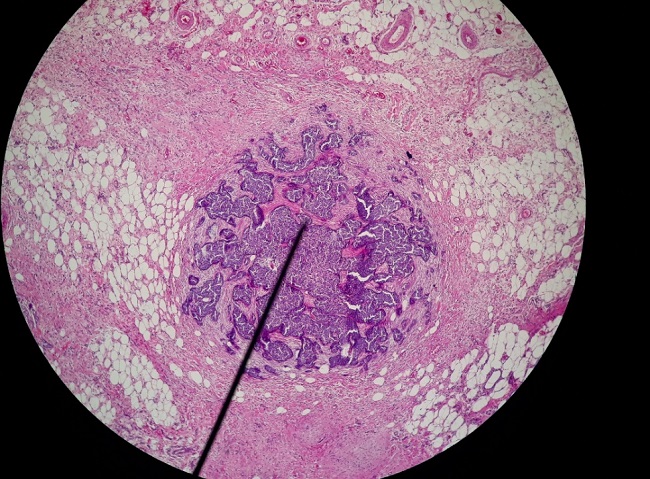

El examen histopatológico evidenció una población sólida de células epiteliales dispuestas en pequeños nidos, sábanas e hileras separadas de abundante tejido fibroso o desmoplasia, muchas de las células (80%) con núcleo excéntrico en forma de medialuna y citoplasma claro bien delimitado PAS+ mostrando presencia de mucina intracitoplasmática. Se evidenció las mismas células en linfonódulo regional inguinal (Figura 3, 4 y 5).

El diagnóstico fue carcinoma de células en anillo de sello con macrometastasis a linfonódulo inguinal.